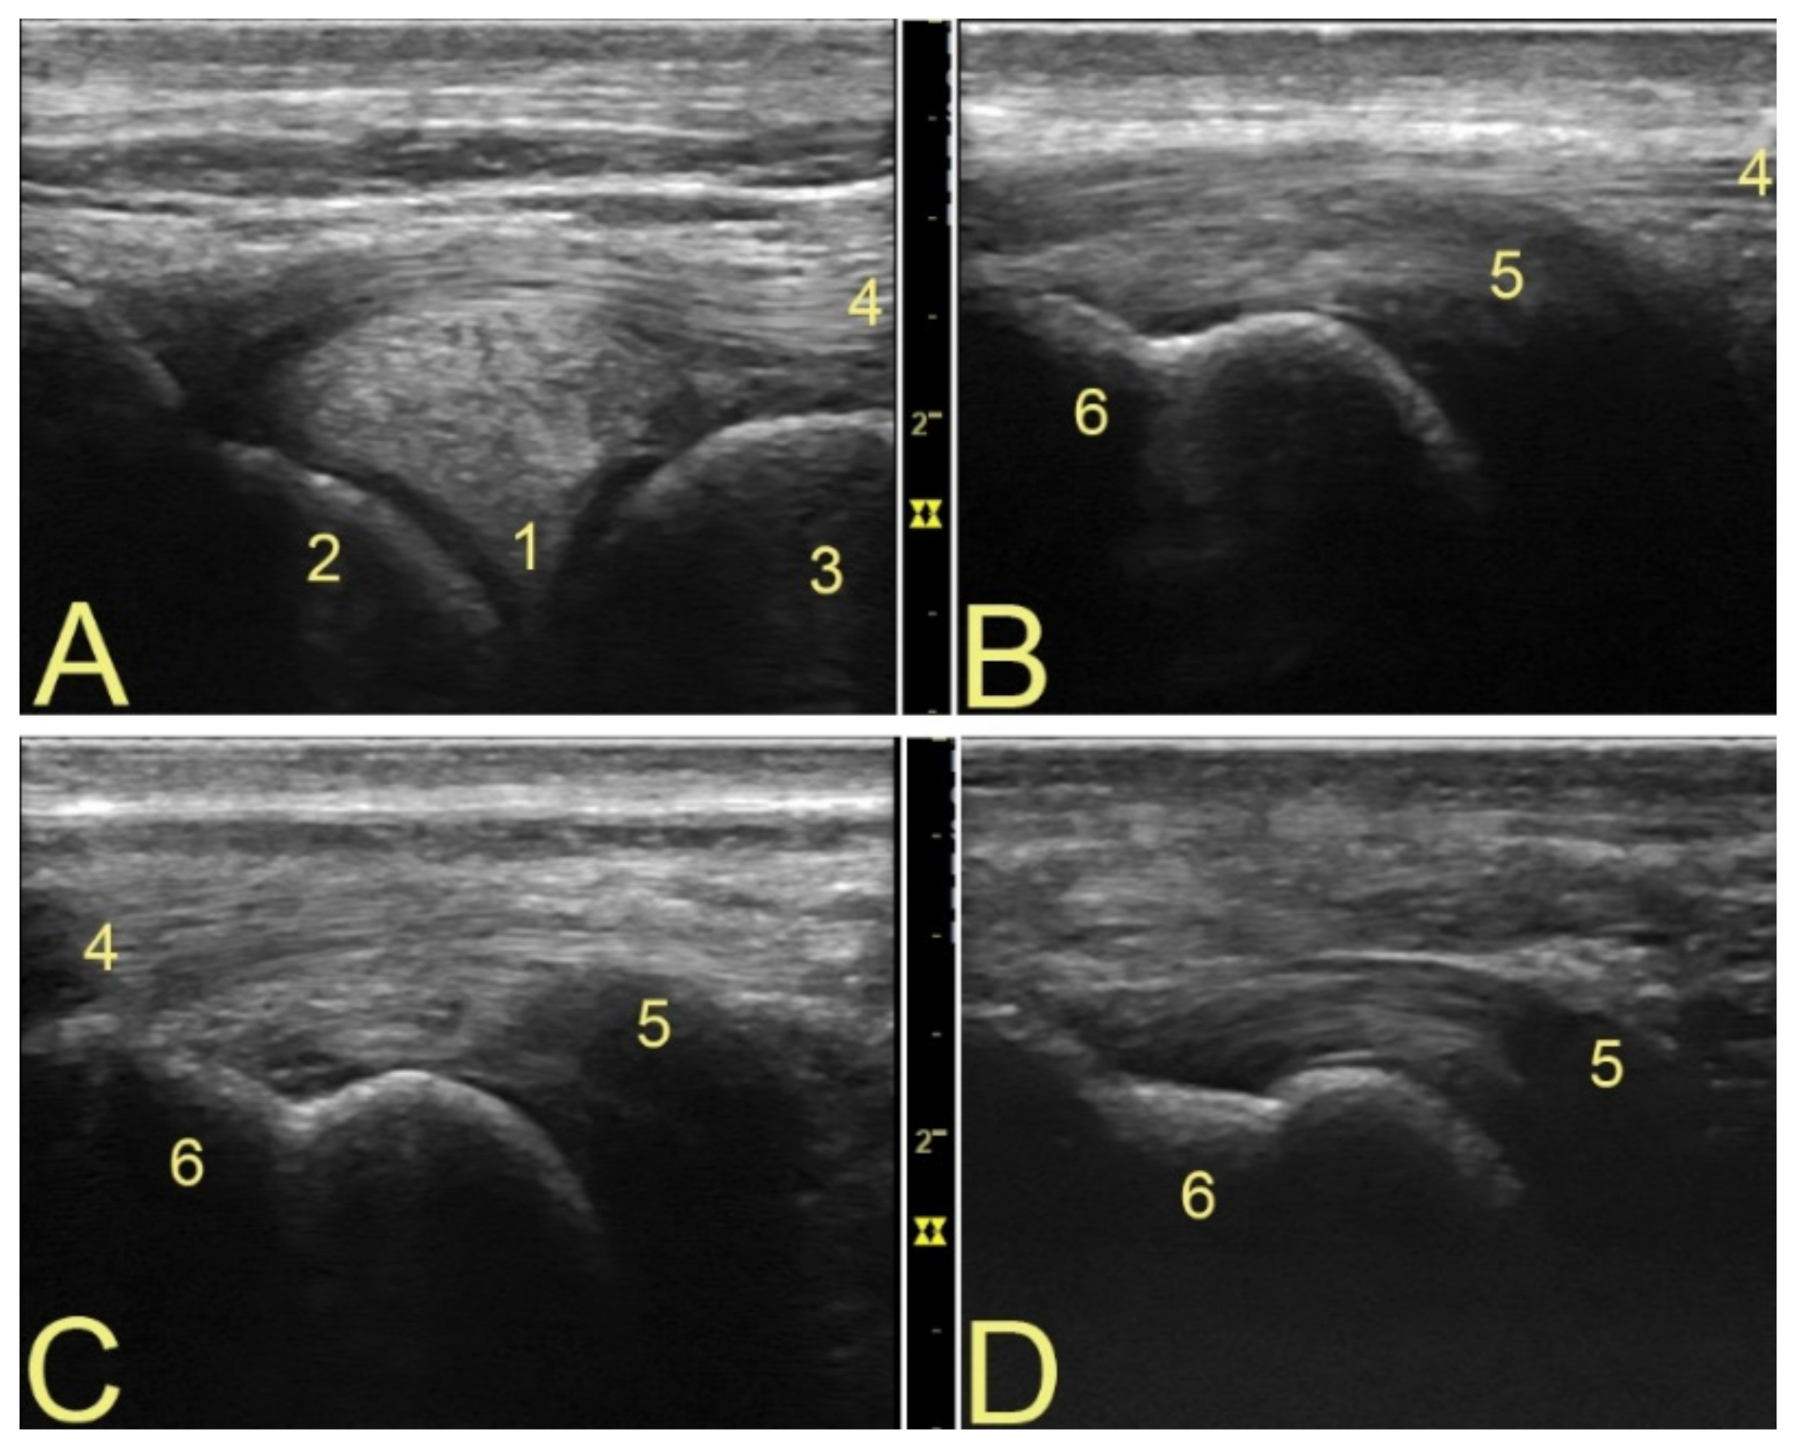

3.1. Anatomical Landmarks for Probe Positioning and Technical Settings

3.2. Popliteal Complex Characteristics